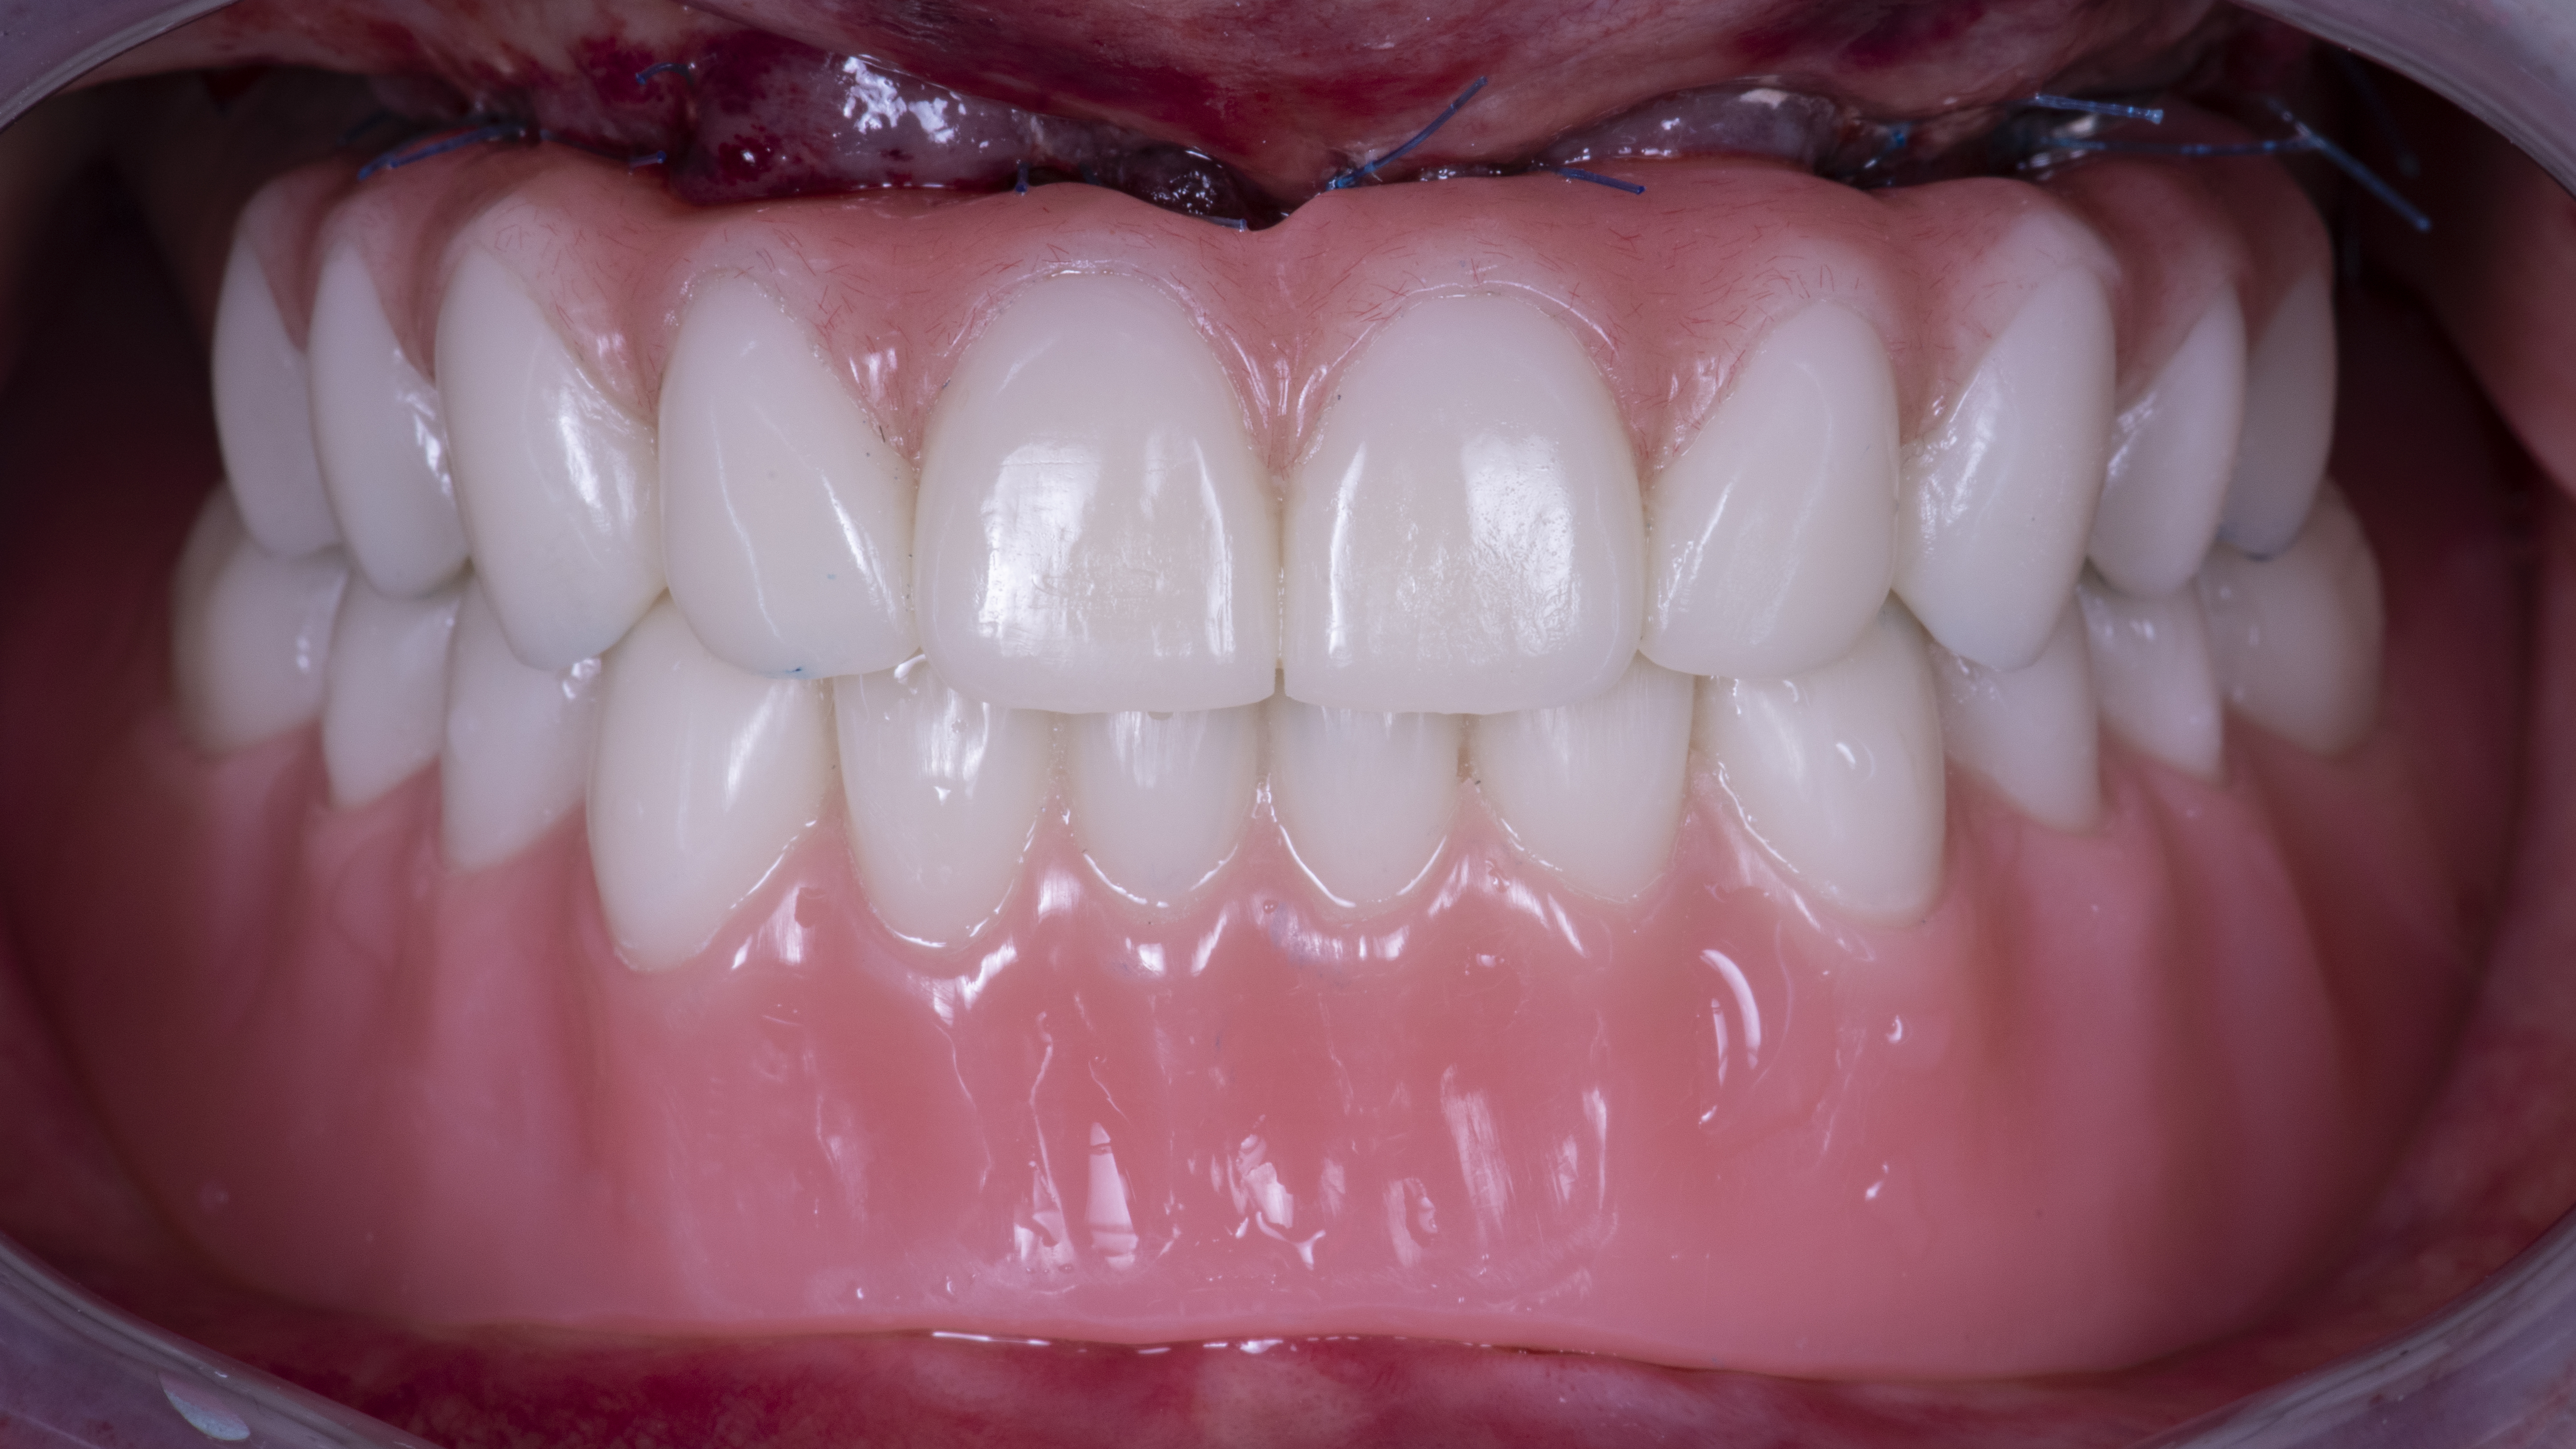

Le protesi definitive sono state infine prodotte in zirconia multilayer infiltrata la quale viene stratificata solo nella parte rosa (Fig. 20, 21, 22).

Fig. 21. Protesi definitive avvitate in zirconia monolitica stratificate solo nella componente rosa

Fig. 22. Situazione finale aspetto extraorale